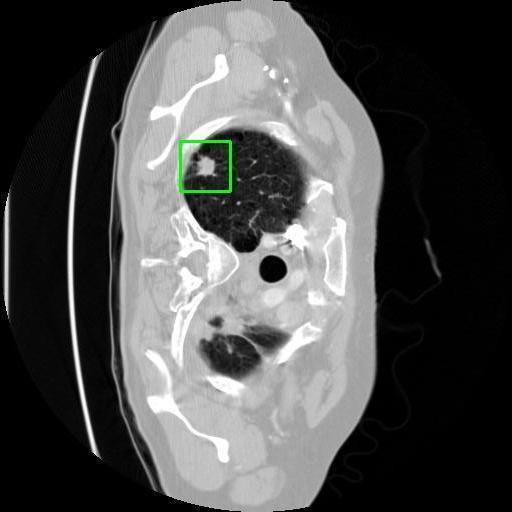

We developed an AI-based system using deep learning models for analyzing lung CT scans to detect and classify pulmonary nodules. We chose the YOLOv11 architecture for its enhanced object detection capability and adapted it specifically for medical imaging, incorporating pixel-level precision and severity classification.

Classification into three severity levels with colored bounding boxes.

Designed a severity classification system that categorizes nodules into null, moderate, and severe using colored bounding boxes, assisting in rapid clinical decision-making.